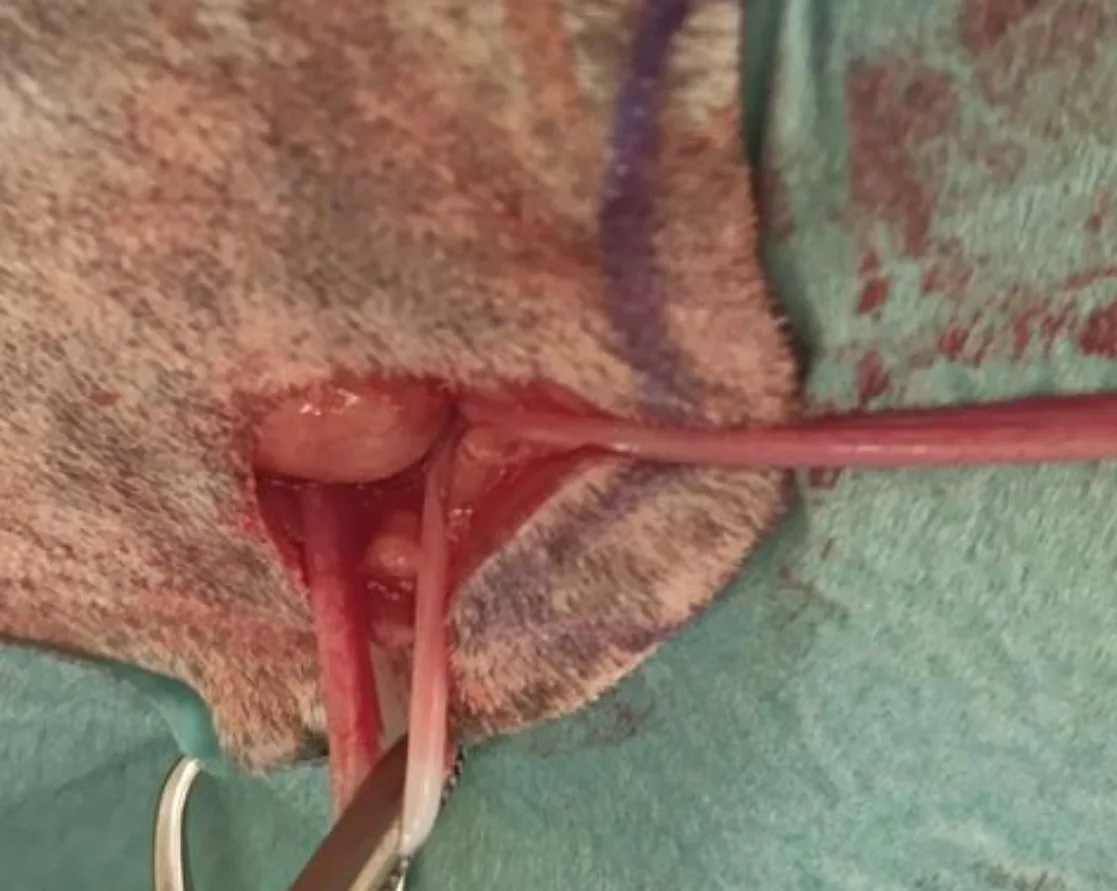

Step 5: Ligate the Ovarian Pedicle on the Contralateral Ovary

After identification and exteriorization of the right uterine horn and ovary, create a hole in the mesovarium, then place 1 straight and 1 curved Halsted mosquito forcep across the ovarian pedicle ≈1-cm dorsal to the ovary. Apply 2 ligatures using a 2-0 absorbable monofilament suture on the ovarian pedicle, which should then be transected between the hemostats.

Author Insight

Following the path from the left uterine horn to the uterine body will help to more easily identify the right uterine horn and ovary.